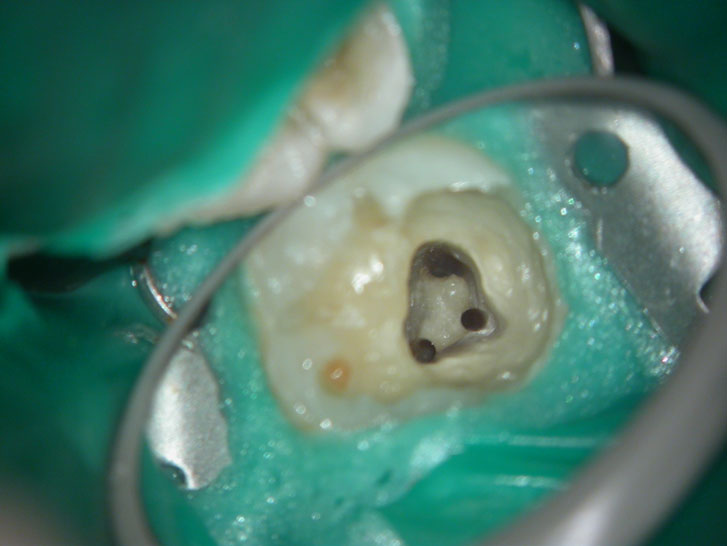

Residual caries seen after temp removal.

After caries removal

Cotton pellets placed over the palatal and Disto-buccal orifices to prevent the instrument from slipping into those canals.

Fractured instrument in mesio-buccal canal

Fractured instrument removed with ultrasonics